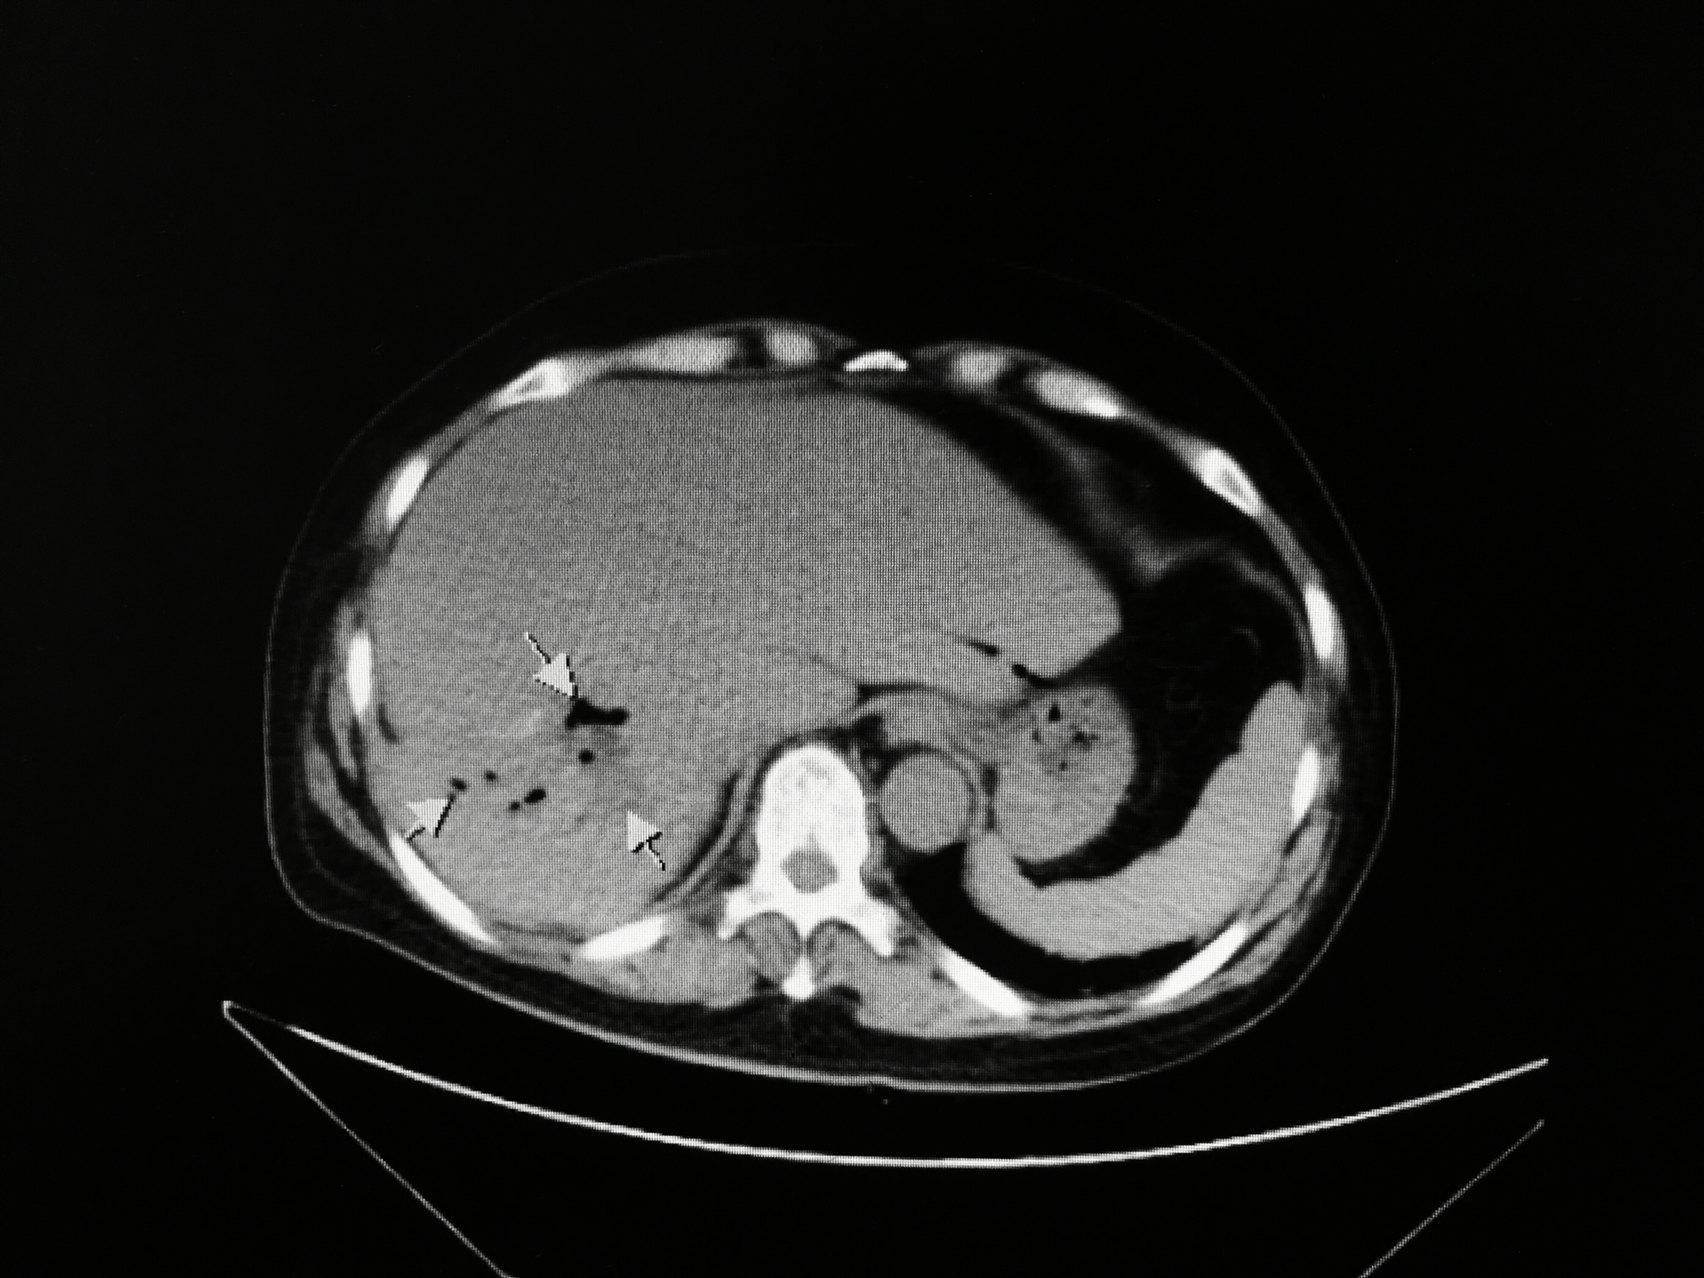

肝内胆管结石的是是非非!

1704x1278 - 246KB - JPEG